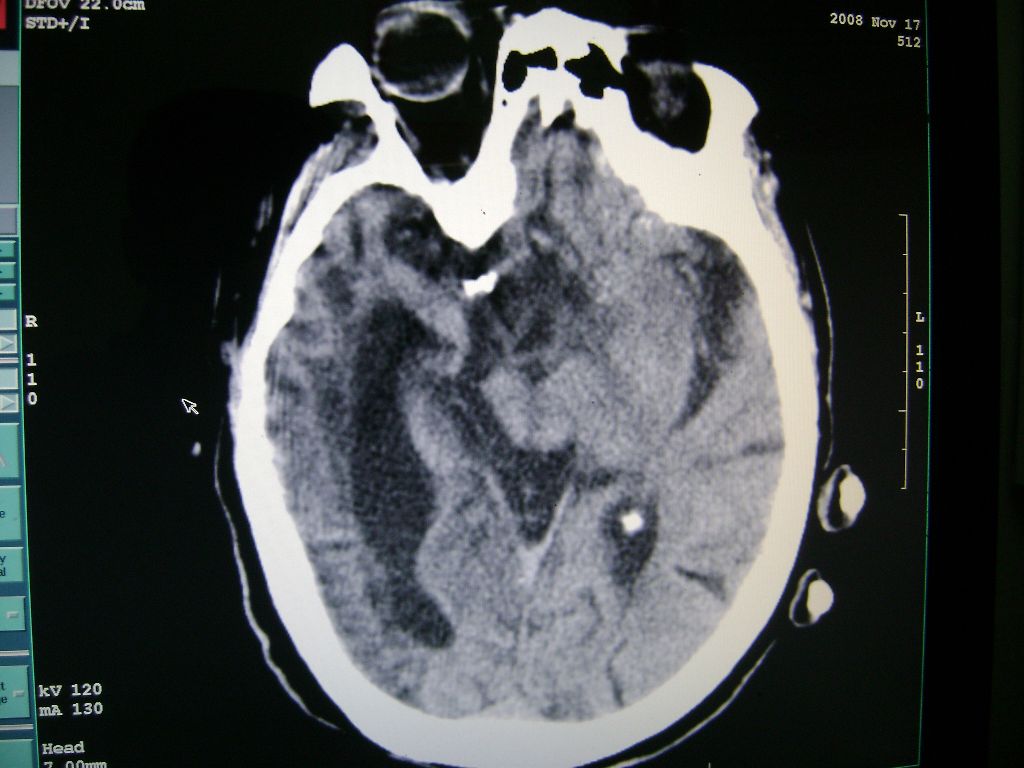

标题: CT16663:F 77 昏迷不醒,各位老师看咯! [打印本页]

f 77 昏迷不醒

出血性脑梗塞

出血性脑梗塞!

右侧额颞枕顶叶脑软化灶,脑萎缩,大脑中动脉壁钙化。

右脑软化灶,考虑再次梗塞,高密度灶出血?钙化?。。。量ct值,改窗宽,位

右脑软化灶,考虑再次梗塞,右顶叶高密度影不像是出血,密度很高,建议量ct值!

右侧半球陈旧性卒中,不除外伴有新病灶,左额叶梗塞,双侧大脑中动脉钙斑

右侧额颞枕顶叶脑软化灶,脑萎缩,大脑中动脉壁钙化。不支持出血(密度高,边界清且局限)顶枕区似有新发梗塞,建议核磁

1)右侧额颞枕顶叶脑软化灶;其内高密度影,多为钙化灶。2)脑萎缩。3)大脑中动脉钙化。

再次脑梗死,右侧额颞枕顶叶脑软化灶,高密度考虑钙化

右侧陈旧脑梗塞伴脑萎缩。脑内点状钙化。大脑中动脉壁钙化灶。无出血灶。

1)右侧额颞枕顶叶脑软化灶并钙化灶可能。2)脑萎缩。3)大脑中动脉钙化。 -